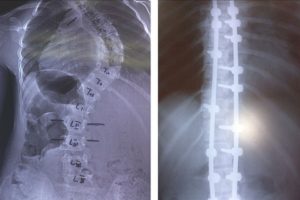

При установке видоизмененного дистрактора Харрингтона важно правильно выбрать точки опоры крючков, так как технические погрешности могут привести к неудовлетворительному исходу.

Нижний опорный позвонок должен быть расположен параллельно поверхности крестца, это дает возможность установить стержень дистрактора вертикально или слегка наклонно в сторону выпуклости деформации. Дистрактор нельзя устанавливать наклонно в сторону вогнутости. У 2 больных мы допустили такую ошибку. У больной К.

вся дуга не была захвачена дистрактором и он имел наклон в сторону вогнутости деформации, что не позволило лучше корригировать деформацию и привело к значительной потере коррекции.